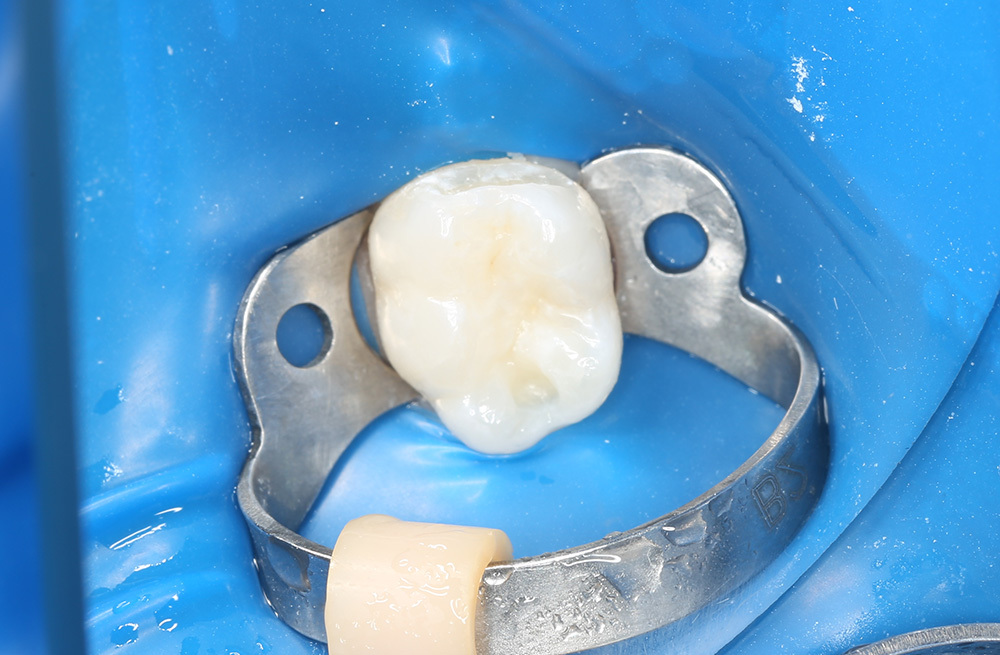

Пломбирование кариозного дефекта коренного зуба с сохранением здоровых тканей